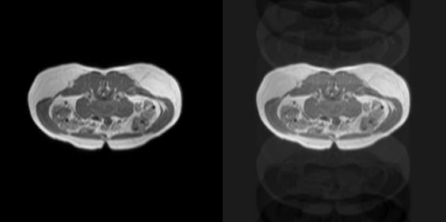

Retrospective MoCo in Liver MRI via U-Net and GAN

Liver MRI plays a crucial role in diagnosing various diseases; however, motion artifacts caused by patient movement during scanning can significantly degrade image quality, leading to misdiagnoses and additional scanning costs. This study explores a deep learning based retrospective motion correction (MoCo) approach using U-Net and Generative Adversarial Networks (GANs) to reduce motion artifacts in liver MRI images. Motion artifacts—including regular moving motion, ghosting effects, and spiking distortions—are simulated using TorchIO to generate training and validation datasets. The proposed model integrates Fully Convolutional Networks (FCNs), U-Net, and Patch-GAN to enhance feature learning through adversarial training. Additionally, perceptual loss is incorporated to test to improve the model’s ability to retain high-level details. The performance of the models is evaluated using the Structural Similarity Index (SSIM) to quantify image quality improvements. The study aims to demonstrate that deep learning-based MoCo can enhance liver MRI interpretation accuracy, reduce the need for repeated scans, and improve diagnosing efficiency while minimizing costs associated with motion artifacts.